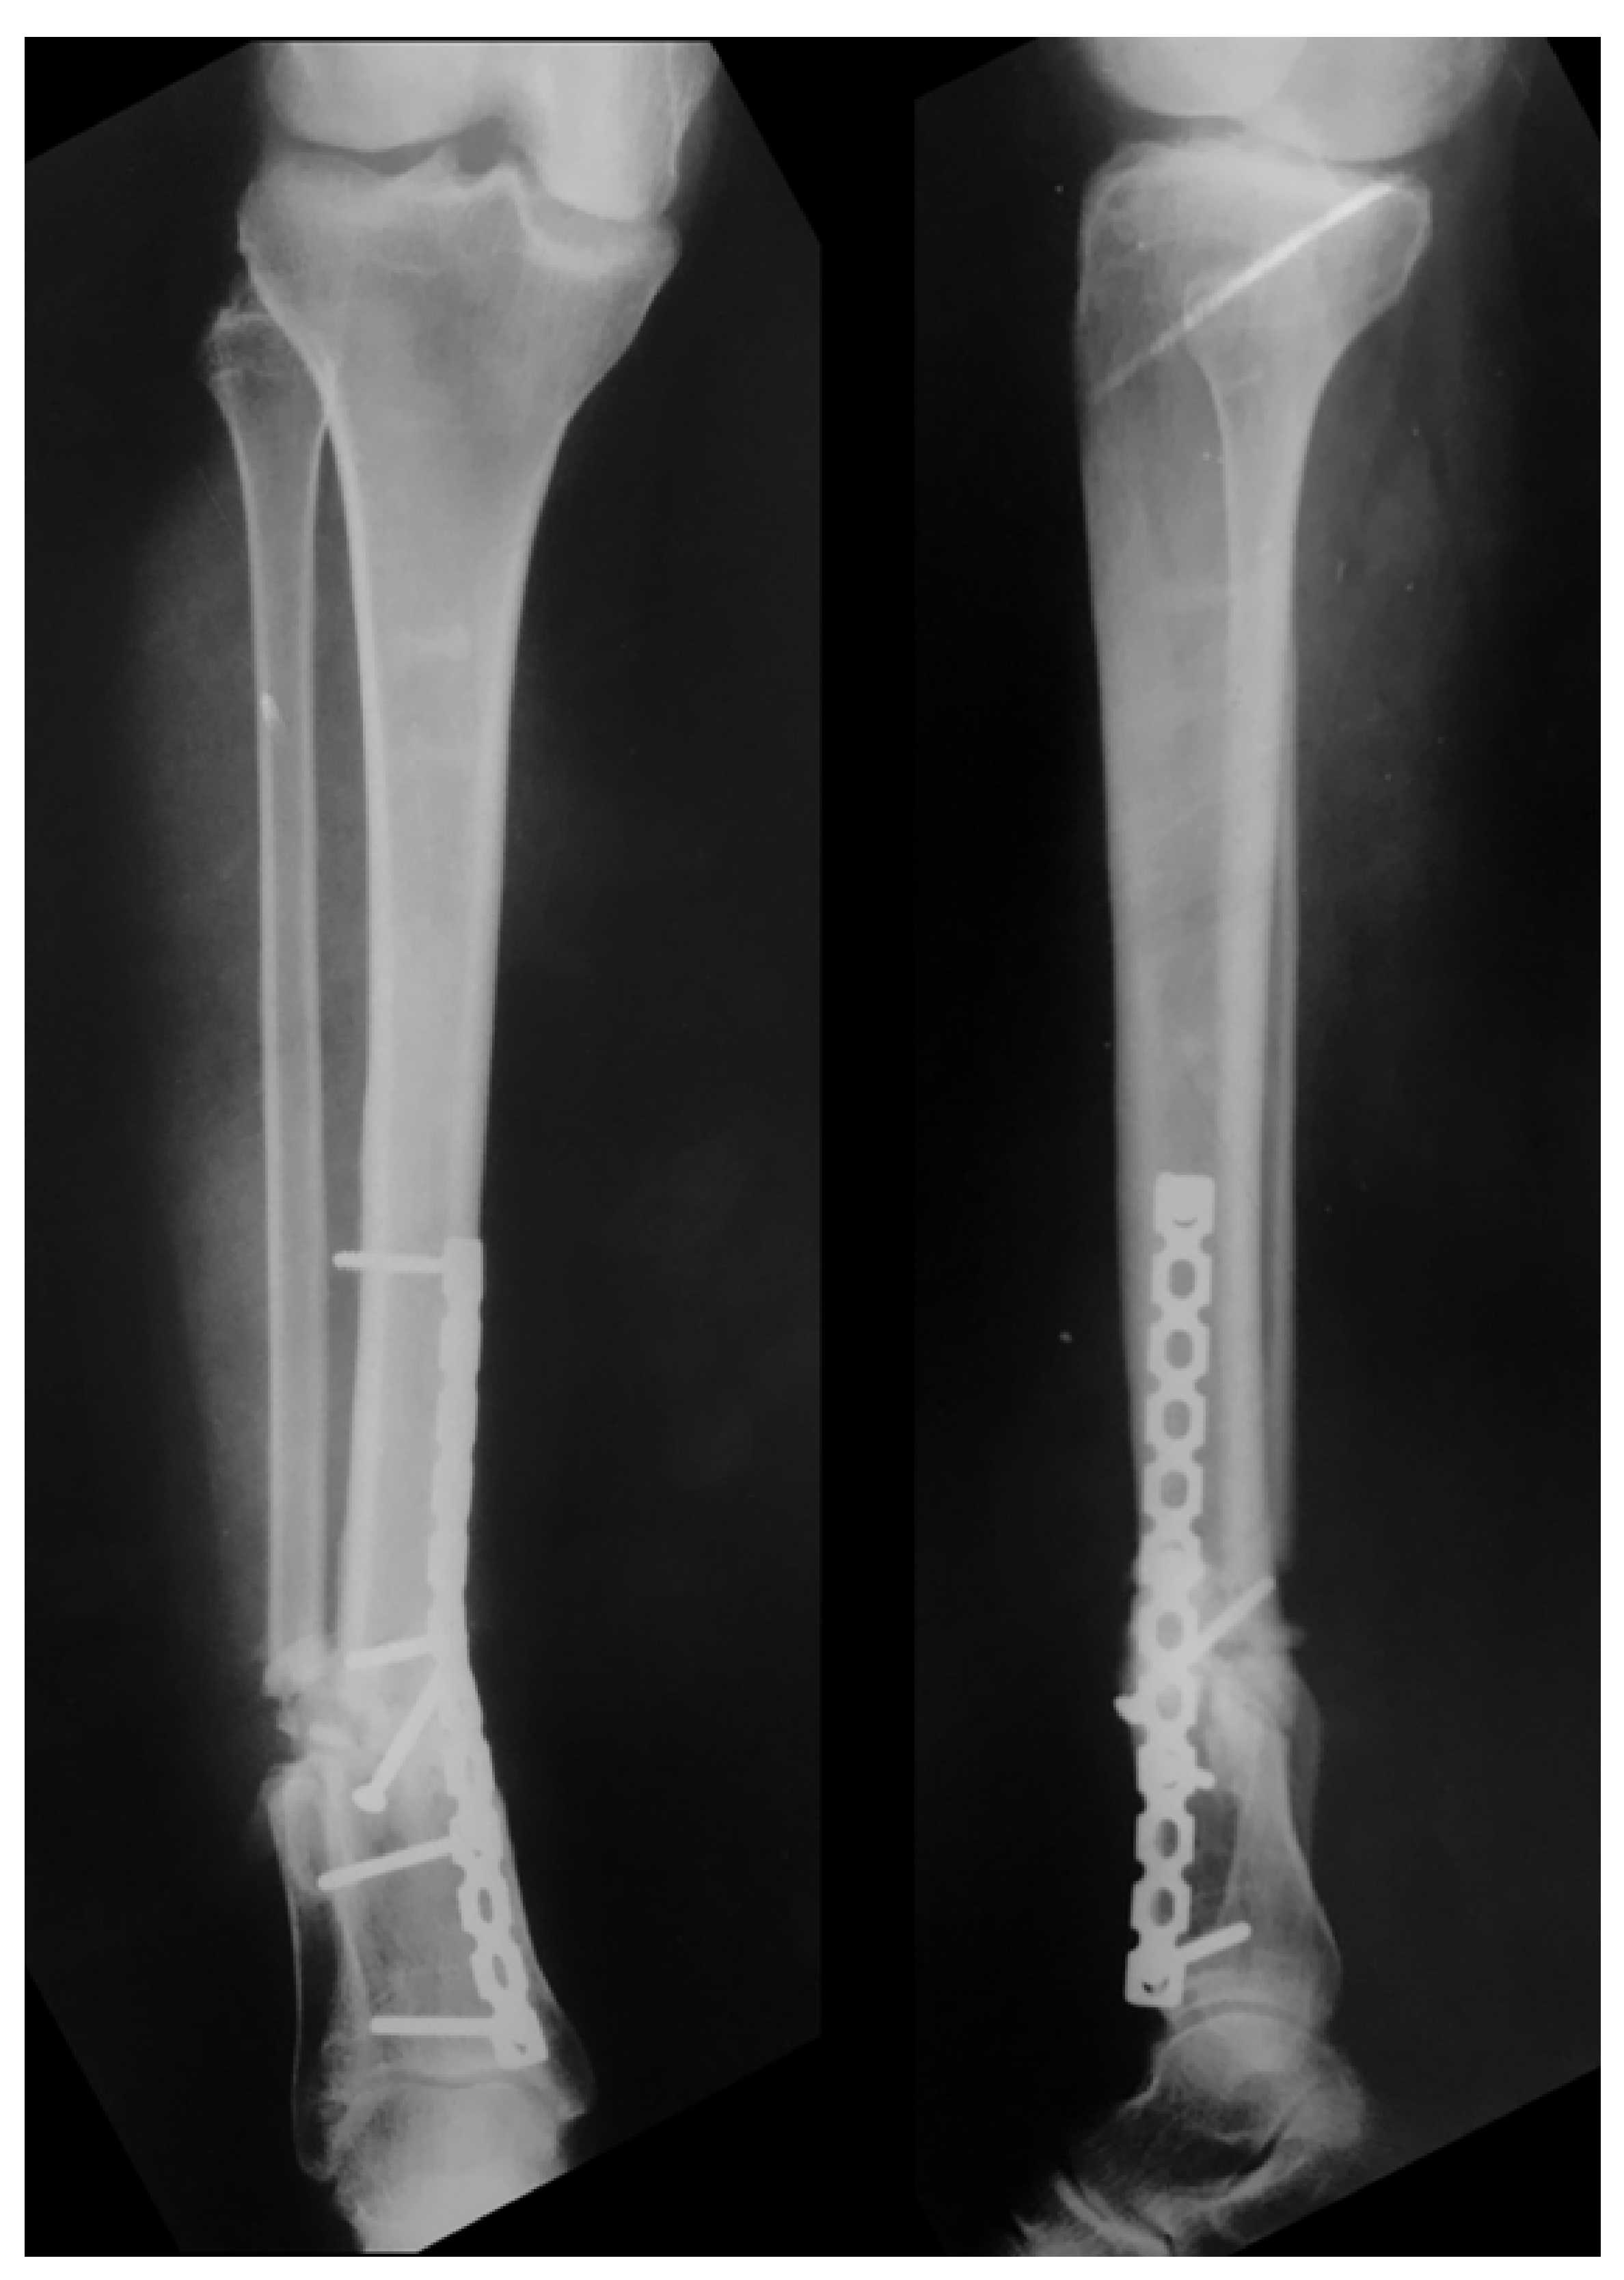

2. Case Report